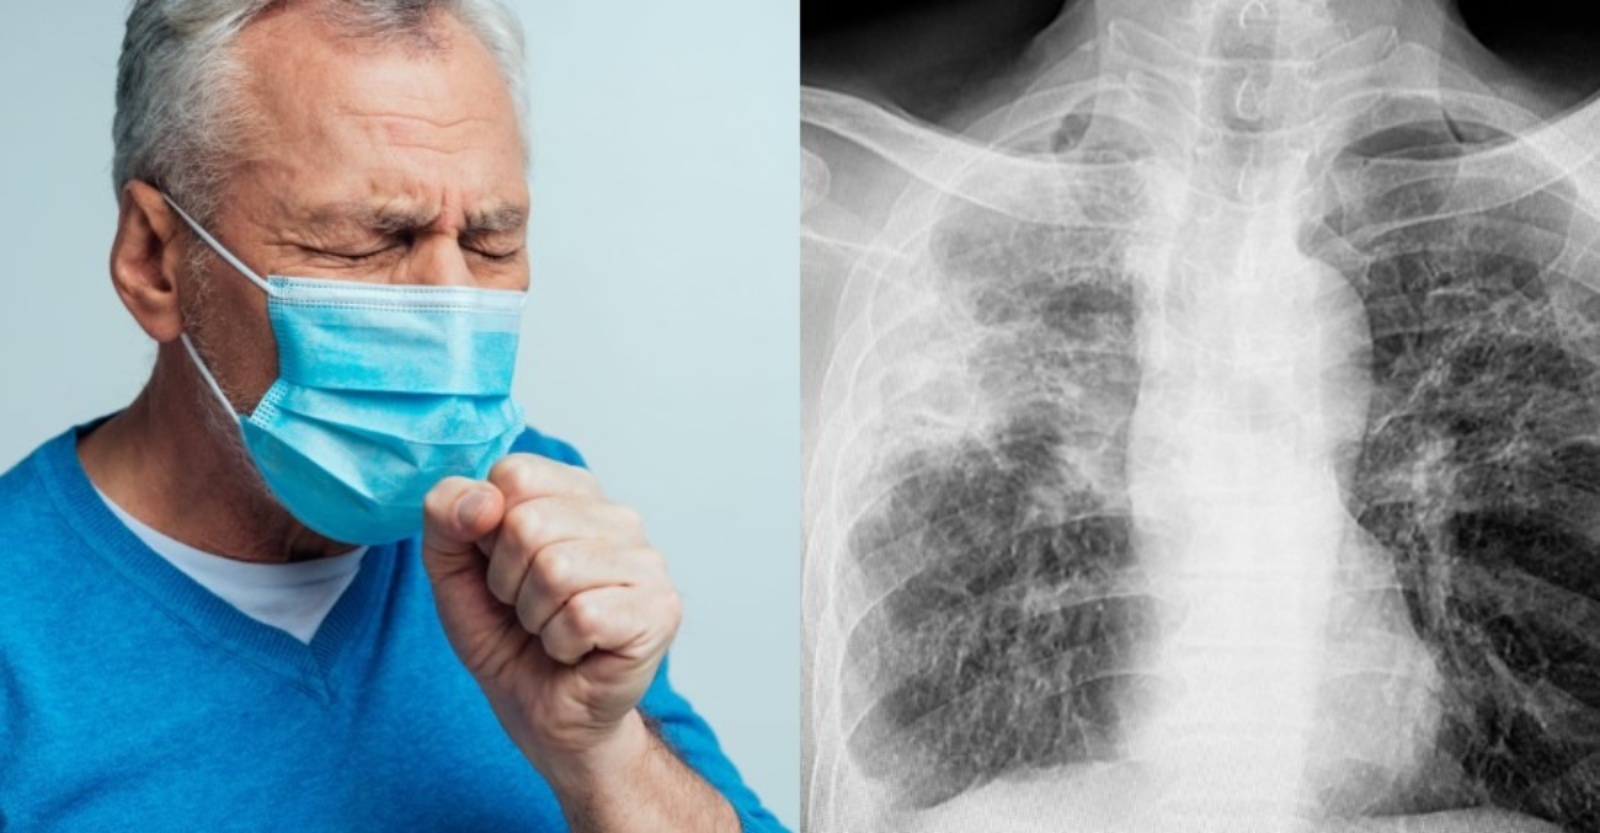

Tuberculosis (TB) may not spread as easily as influenza or COVID-19, but prolonged close contact in crowded and poorly ventilated spaces can still allow the disease to circulate quietly in communities.

According to Dr Lo Shan Min Consultant Physician & Respiratory Medicine at Oriental Melaka Straits Medical Centre, TB spreads when someone with an active infection coughs, speaks, or sneezes.

“But transmission usually requires extended exposure in indoor spaces, not casual encounters. Recognising this difference is critical to preventing further spread,” he said.

Dr Lo emphasised that one of the earliest and most common signs of active pulmonary TB is a persistent cough lasting more than two weeks. Other symptoms include night sweats, low-grade fever, fatigue, unintentional weight loss, and in more advanced cases, coughing up blood-stained sputum or chest pain.

TB is less contagious than viral respiratory diseases, but prolonged exposure in dense indoor environments increases the risk of transmission. Dr Lo noted that households, workplaces, dormitories, prisons and crowded community events can facilitate transmission when someone with active TB is present.

The U.S. Centers for Disease Control and Prevention states that TB bacteria are transmitted via airborne particles, which linger longer in poorly ventilated areas, making prolonged exposure a key risk factor.